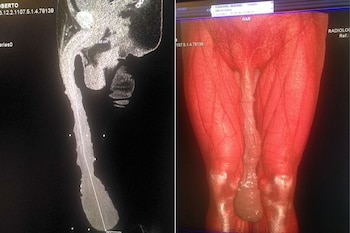

Roberto Esquivel Cabrera se sienta con dificultad. Se acomoda una y otra vez en la banqueta. Lo hace automáticamente, sin pensarlo, desde que su pene comenzó a crecer de manera desproporcionada. Hoy alcanza casi el medio metro de longitud, todo un récord.

El hombre superó con creces a otro que creía tener el miembro más largo: se trata del actor norteamericano Jonah Falcon, cuyo pene alcanzaba los 24 centímetros flácido y 34 centímetros erecto. El de Cabrera tiene 48 centímetros.